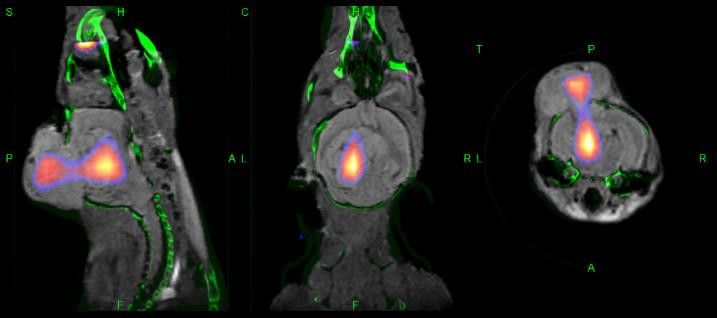

乳腺癌模型-肿瘤成像

InSyTe FLECT/CT能够评估荧光染料Cy7

标记的活化血小板靶向抗体肿瘤的靶向性和成像能力。